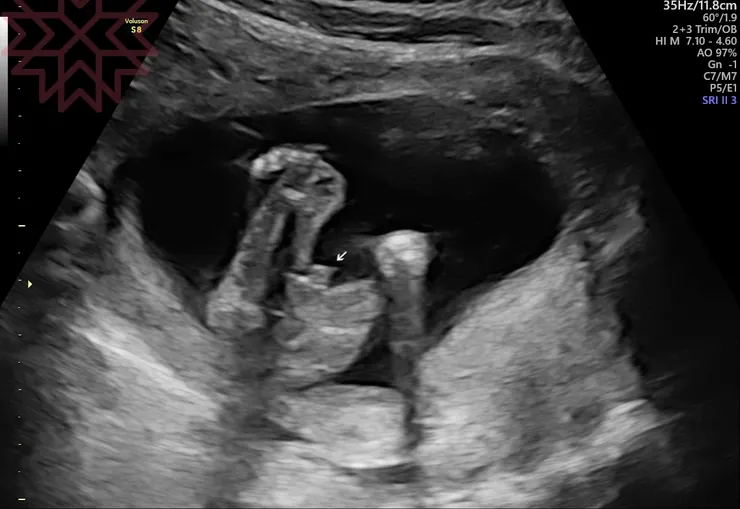

最後我的結果是......登登登登......

其實開箱幾個小時後,我們兩個都有淡淡的失落感,可能是少了一種性別的可能性吧(買回家就會覺得另一個比較好的盲點?),果然男生女生都有魅力,還討論起如果是雙性人如何的事XD~自己感覺科學見解有點準,大家可以試試看,但其實光是想男生好、女生好已經很困難,我想N久想不出來,結果收到上天寄來一隻男獺獺XD